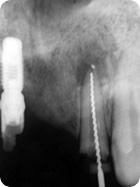

Retratamento Endodôntico

Retratamento Endodôntico 1

Retratamento Endodôntico 2

Retratamento Endodôntico 3

Retratamento Endodôntico 4